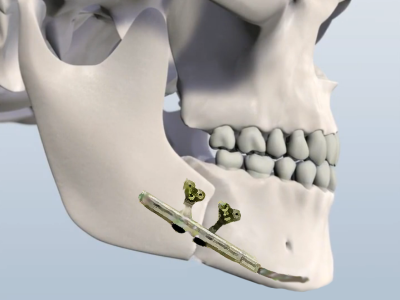

Distraction osteogenesis procedure in Hyderabad for bone lengthening

Distraction Osteogenesis

Distraction Osteogenesis is an established scientific method of elongating or increasing bone length or producing new bone without using any bone grafts, for correcting various facial deformities.